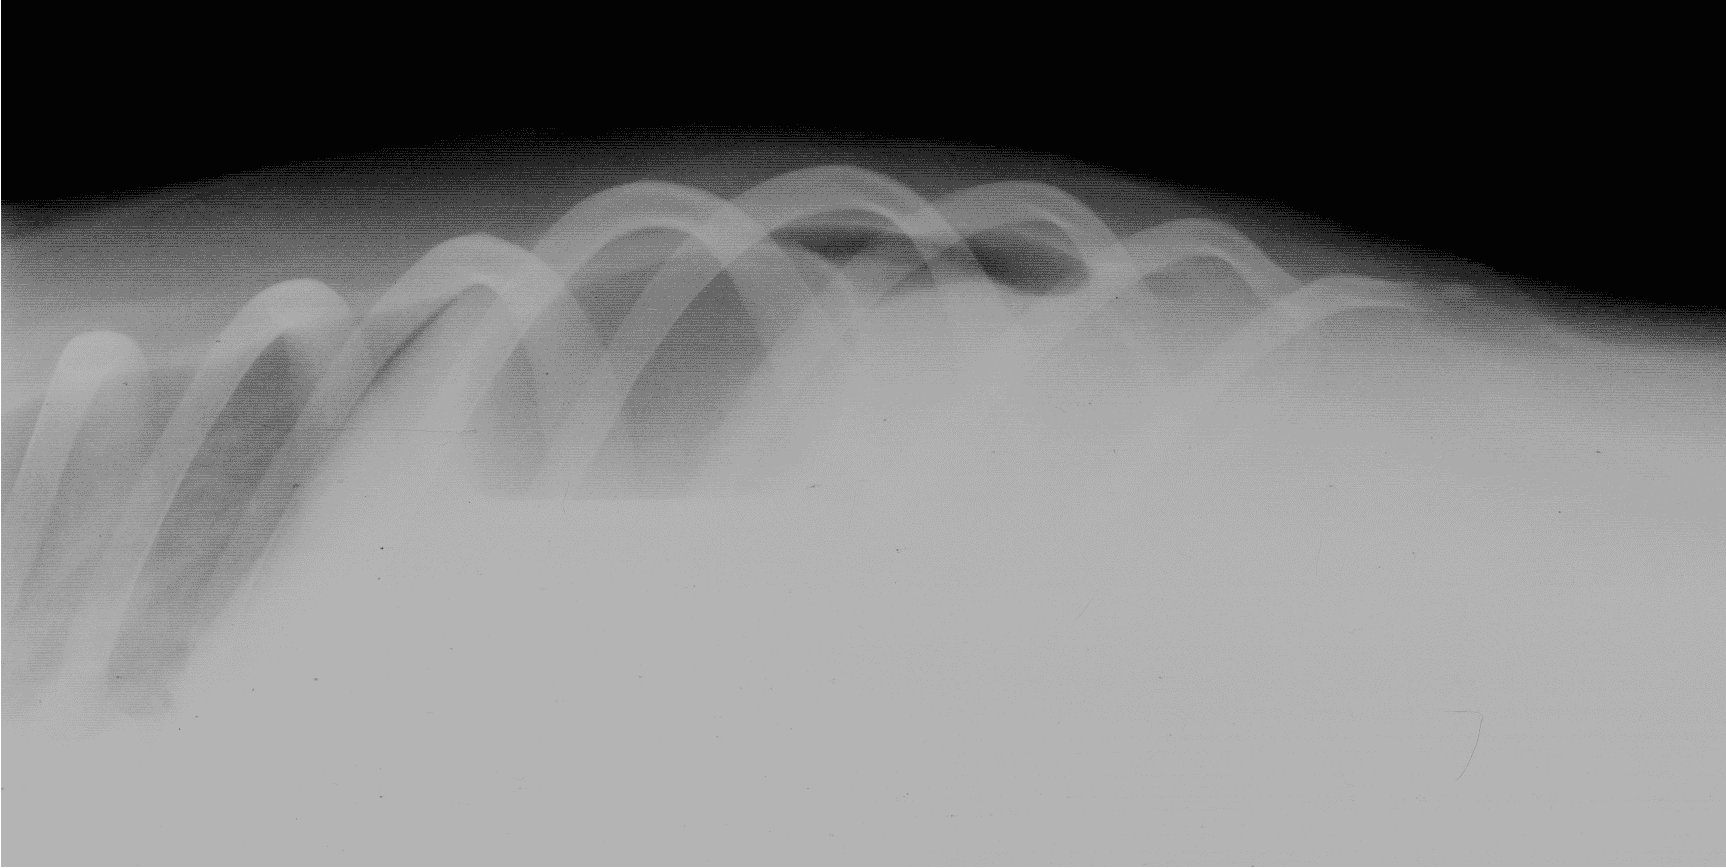

Proximal duodenal and gastric outflow obstruction can cause persistent vomiting with low serum Na, Cl and K; these electrolyte changes should be considered very suspicious even in the absence of imaging findings for obstruction. Abdominal radiographs should include orthogonal views (a right lateral and a ventro-dorsal or dorso-ventral image). Classic radiographic signs for surgical disease can include the “double bubble” for GDV ( Figure 1), two distinct populations of small intestine with obstruction (small and large diameter gut evident with, for example, intussusception, intestinal mass or foreign body; Figure 2) or free abdominal gas with a lack of serosal detail with septic peritonitis. Free abdominal gas can be very obvious ( Figure 3) but a more subtle pneumoperitoneum is best recognised using a horizontal beam radiograph with the patient in lateral recumbency ( Figure 4). Of course, a lack of radiographic changes does not fully exclude a gastrointestinal emergency and abdominal ultrasound can help to identify the problem or guide further diagnostics (eg abdominocentesis of free abdominal fluid). Septic peritonitis due to intestinal leakage will result in an effusion with cytological identification of neutrophils and/or bacteria. If intracellular bacteria can’t be definitively identified but there remains a concern for septic peritonitis, glucose and lactate assessment can be helpful.